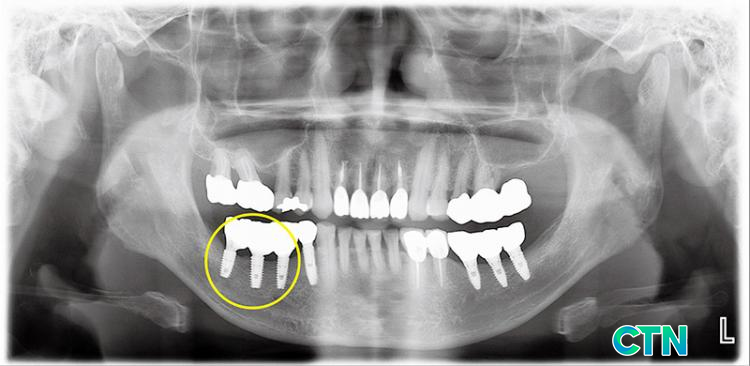

öƮ ֺ öװ ո ƹ Ѵ. ̷ ռ ȯ ڰ ֱ ġ ߿ϴ. öƮ ϴ ƴϴ. ٷ öƮ ǥ ִ Ư ̴. öƮ Ǿ ̹Ƿ, öƮ ǥ鿡 鷯 ֵ Ǿ ִ. ̷ ǥƯ öƮ ǥ Ǿ յ ٴ´. ̸ ؼ ó ĸ ֺ ո β 1.5mm~2mm̻ Ȯϴ ߿ϴ.

ĸ ռ öƮ ؾ ϴµ, öƮ ġƿ ǥ鿡 缱 ְ, ̰ Ǿ ִ. ġó ־ ̴´ٰų ó , ֺ ո Ƴ Ÿ ؾѴ. ü Ӹ ƴ϶, ո ٽ ȸ ʱ 쿡 ո ̽ļ ʿ ִ. Ƿ öƮ ĸ 䱸Ǵ Ʈ ƴ϶, ġ Ⱓ ִ ո 翡 ̽ ̵ ö Ƿ ̵ ̶ ִ.

öƮ ĸ ϱ ߿ öƮ ĸ ִ ո ´. β ո öƮ ĸ ־ ʼҰ Ҵ.

ڷ(1) ĸ 3 öƮ ֺ ٰ ġ ȯڴ. ʾƷ öƮ ֺ Ǵµ, ̴ öƮ ֺǻ ǹѴ. ո Ȯ ä öƮ ĸϿ Ұ 3 öƮ ǥ Ǹ鼭 ǰ ֺ ȴ. ٷ ʿ ° öƮ ֺδ ϰ ǰ , ̰ ο ̾ ȴ. ᱹ öƮ ϰ 3 ո ̿ β ٷ ̽ Ͽ. ̽ĵ ֺո з Ͽ Ǵ ϱ ݼӸ ̿Ͽ , 6 ݼӸ öƮ ĸߴ. (2) öƮ ĸ ϼ ¿ Կ ij.